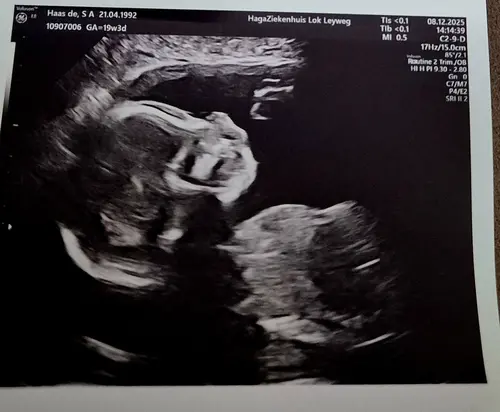

Hier afgelopen maandag gehad met 19+2 weken, ik ben 2 mei uitgerekend. Wij verwachten na een jongetje nu een meisje 馃┓馃グ. De bovenste zie je haar ruggetje heel goed en de onderste is van het geslacht. Wij zijn super blij dat ons zoontje een klein zusje krijgt! 馃┓馃グ